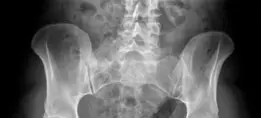

- صورة الحوض الأمامية الخلفية (Anteroposterior pelvic X-ray) : تكشف عن بروز الجدار الخلفي للحُق (Posterior overcoverage) وتغطية الحُق بشكل عام. يمكن أن تظهر أيضًا تعظم الشفا الحقي.

صورة شعاعية أمامية خلفية للحوض تظهر بروز الجدار الحقي الخلفي الأيسر (الأسهم) وتعظم الشفا الحقي الخلفي العلوي.

صورة شعاعية جانبية عبر الطاولة تظهر الجدار الخلفي البارز للحُق الأيسر.

صورة شعاعية جانبية عبر الطاولة توضح بروز الجدار الخلفي للحُق الأيسر.